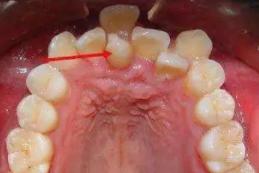

牙缝里长出的小肉球又是啥?

牙缝小肉球哪来的?

龈乳头增生,大多数情况下是细菌引起的炎症引起。

塞在牙缝的食物残渣不断挤压牙龈,牙菌斑在牙龈边缘不断刺激,使牙龈红肿。

一旦牙缝间牙龈红肿,要克服那种不舒服的感觉,坚持用牙线、水牙线这些工具牙缝清理干净。可以使用含氯己定的漱口水漱口,这些是我们在家就能做到的。还得去专业机构洗牙,必要时龈下刮治。